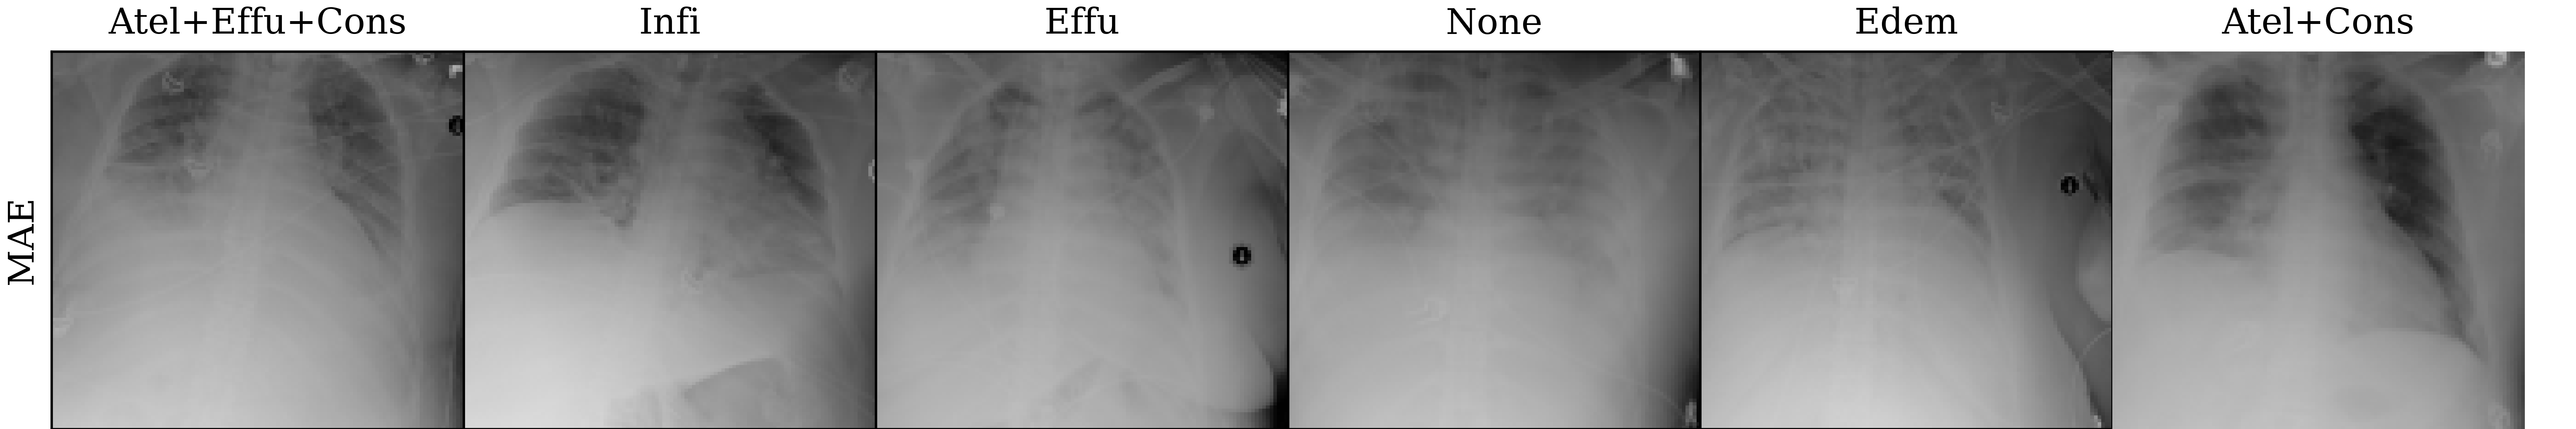

Lastly, we visualize the nearest neighbors in the embedding space of MoCo-v3 and MAE pre-trained models to yield insights into the pre-trained representations. To this end, we extract the last layer representations (after the layer norm) for both the train and test sets of ChestXray14. For each image in the test set, we compute the 5 nearest neighbors from the train set. The results are visualized in Figure 4, which reveals that the nearest neighbors of both MoCo-v3 and MAE largely preserve the overall shape of the query image. Additionally, we also perform a quantitative analysis by assigning the label of the nearest neighbor as the prediction for the query image. Under this nearest neighbor classification setting, MoCo-v3 has a slightly higher mAUC than MAE (52.7 vs 52.3), indicating that its pre-trained features are more linearly separable. This finding is in line with the observations made by He et al. (2022), who observed that the MoCo-v3 features are more linearly separable than MAE features. However, it is worth noting that despite MAE features being less linearly separable than MoCo-v3 features, the former captures more powerful non-linear features. This translates to stronger downstream models when the networks are fine-tuned instead of being used as fixed feature extractors, as evidenced by the superior fine-tuning results presented in Section 4.1.